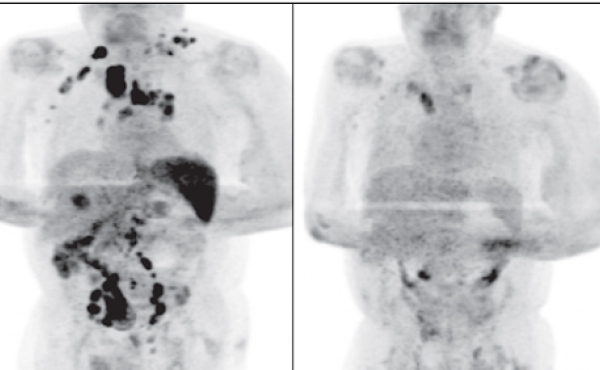

El caso, que fue publicado en la revista British Journal of Haemathology, corresponde a un hombre de 61 años que desarrolló una respuesta antitumoral que le ayudó a remitir parcialmente el linfoma de Hodgkin que sufría.

De acuerdo con el reporte, el hombre estaba en el estado III de gravedad, es decir, que su cáncer se encontraba bastante extendido por el cuerpo abarcando áreas de ganglios linfáticos a ambos lados del diafragma, tanto arriba como abajo del diafragma.

La sorpresa de los médicos que lo trataron se dió cuatro meses después cuando el paciente regresó a consulta médica y los ganglios inflamados habían disminuido de forma drástica. Los científicos creen que la infección por SARS-CoV-2 desencadenó una respuesta inmunitaria y terminó ayudando a que su cuerpo combatiera el cáncer.